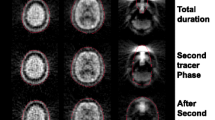

Detailed methods have been published elsewhere (Georgiadis et al. 2006), but, briefly, 11 healthy right-handed females (mean age 34, range 21–47) participated after written informed consent according to the Declaration of Helsinki. Experimental procedures were approved by the Medical Ethics Committee of the University Medical Center Groningen. Five hundred MBq of [15O]-H2O was injected at 8 ml/s into the right antecubital vein. Eight 2-min scans were made with 8 min in between. Scans consisted of six 10-s frames and one 1-min frame. Scans 2–8 had an extra 30-s frame at the start to measure background activity. Injection was at the start of the first 10-s frame.

After background correction, all resulting scans had seven frames. Spatial processing and statistical analysis were done with SPM (http://www.fil.ion.ucl.ac.uk/spm/). The frames within each scan were realigned, and the first 10-s frame was discarded from analysis because of low counts and relatively high variability. The remaining six frames were then summed in all possible permutations of consecutive frames (see also Fig. 6.1). The summed images were spatially normalized (affine only) to the SPM [15O]-H2O template and smoothed with a 10-mm kernel.

Finally, we constructed time-activity curves (TACs) for the activated clusters in order to verify and illustrate the results from SPM comparison of the different intervals (Fig. 6.3). With the program Amide (http://amide.sourceforge.net/), TACs were constructed as follows. First, ellipsoid ROIs were drawn over the activated foci in the sensorimotor area (22.6 mL) and the cerebellum (19.0 mL) on a subject by subject basis. To correct for injected radioactivity dose per scan, we used an ellipsoid covering the whole brain (3.11 L), calculated the mean radioactivity concentration over the final five frames, and divided all time points in the sensorimotor and cerebellar ROI by this value.

Average time-activity curves (TACs) for the two activated clusters in relation to the tasks: in the motor condition the sensorimotor cluster is more dynamic and reaches a higher radioactivity concentration. Count rates were normalized intrascan to the average whole-brain activity concentration in the last five frames. Error bars indicate standard deviations over subjects

Figure 6.1 shows the intervals that were compared (in white) along with the brain activation patterns (t-distribution maps in a lateral glass brain) that resulted from all of these comparisons.

Two robust brain activation loci were present for in the majority of compared intervals: the dorsal sensorimotor cortex and the medial part of the anterior cerebellum. As can be seen in the top rows of this figure, significant rCBF differences were also found with the shortest duration of the time period: 10 s. The 10 s interval that resulted in the largest activation was 30–40 s after injection of the radiotracer. The period compared clearly had a strong influence on the activation maps: both activation clusters were highly variable and the sensorimotor cluster was sometimes completely absent (for periods 50–60 and 50–120 s).

3.2 TAC Analysis

TACs for the two regions are presented in Fig. 6.3. Visual inspection shows clear differences between the two anatomical areas. ANOVA repeated measures of the TACs confirmed this impression, revealing in addition to a strong time effect [F(5) = 49.63, p = 0.02] a strong interaction of time and region [F(5) = 30.49, p = 0.032]. (Interactions time × task and time × task × region could not be investigated due to lack of residual degrees of freedom.)

The sensorimotor cluster reached higher radioactivity concentration in the motor condition than the cerebellar cluster, which was also more stable in time.

The basis for this finding is the different temporal dynamics of the activity concentration in the two regions or, more precisely, the different dynamics of the difference between the curves for the two tasks between the two regions. The difference between the TACs for the two tasks was more or less constant for the cerebellum (Fig. 6.3, left pane), but for the sensorimotor area, the difference between the two curves was clearly larger during the first half of the scan (Fig. 6.3, right pane). This is in agreement with the SPM findings that comparing long intervals works best for the cerebellum and that, by contrast, comparing shorter earlier intervals works best for the sensorimotor area.

It is known that blood flow in the cerebellum is very different from that in the cerebral cortex. In particular, cerebellar CBF (Bauer et al. 1999; Ito et al. 2003; Tomita et al. 1978) and perfusion pressure (Ito et al. 2003, 2000) are among the highest in the brain. Because vascular water is extracted into brain tissue, but clearance from tissue is slow (Wong 2000), the rising phases of the TACs for the cerebellum and sensorimotor area are similar. It is not understood why the higher perfusion pressure in the cerebellar vasculature appears to reduce extraction of labeled water (more horizontal TACs than in the sensorimotor area) rather than to increase it.